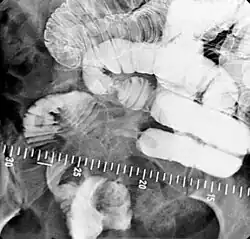

Zunächst wird über eine nasojejunale Sonde ein positives Kontrastmittel (KM) zur Flexura duodenojejunalis (Übergang vom Zwölffingerdarm zum Leerdarm) gebracht. Das Kontrastmittel besteht aus wasserunlöslichem Bariumsulfat. Mit einem zweiten, wässrigen, negativen Kontrastmittel (Methylcellulose) wird die Bariumsulfatsäule durch den gesamten restlichen Dünndarm vorangetrieben. Durch diese Doppelkontrastierung stellt sich das Darmlumen transparent dar, während das Bariumsulfat an den Darmwänden anliegt und diese dadurch begutachtet werden können. Es werden dabei die Lumenweite und das Faltenrelief (Kerckring-Falten) begutachtet sowie Füllungsdefekte, Pelotteneffekte, Verziehungen und Distanzierungen der Darmschlingen zueinander sowie Veränderungen in der Umgebung der Darmschlingen (Fisteln etc.) und Motilitätsstörungen (Hyper- oder Hypomotilität) erfasst. Des Weiteren wird auch die Darmwanddicke beurteilt, die im Dünndarm 2 mm nicht überschreiten sollte.[1]

Zu den Indikationen dieser Untersuchung zählen neben den chronischen entzündlichen Darmerkrankungen[2] und deren Komplikationen (Fistelung, Abszedierungen, Darmverziehungen und Stenosen) auch Mobilitätsstörungen, Divertikelnachweis und die Erfassung tumoröser Wandveränderungen.